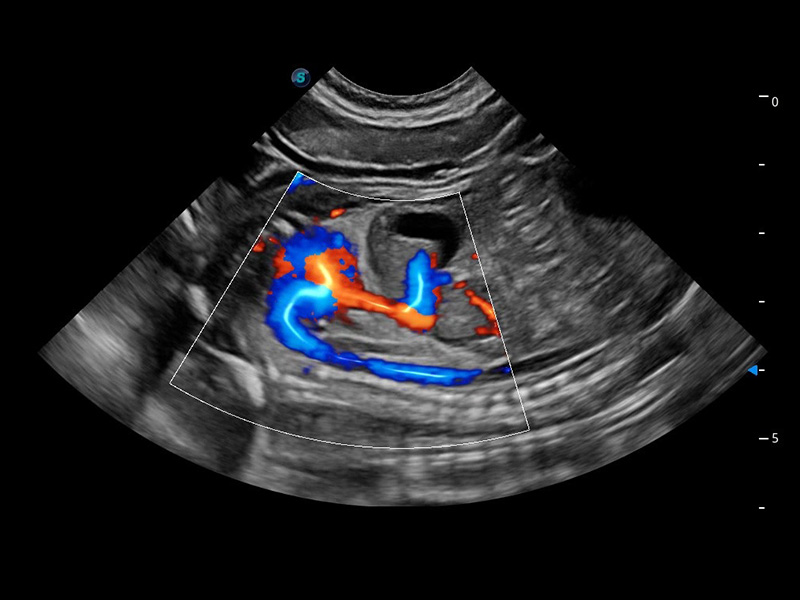

ProPet 60 作為一款高端臺(tái)式動(dòng)物超聲設(shè)備,為動(dòng)物醫(yī)生的日常診斷提供了一系列貼合動(dòng)物臨床需求、解決臨床實(shí)際問(wèn)題的高級(jí)成像功能。憑借全系列高清探頭,滿足醫(yī)生對(duì)腹部、心臟、生殖、淺表、肌骨等成像的所有需求,切實(shí)幫助您提升檢查效率,提高診斷信心。